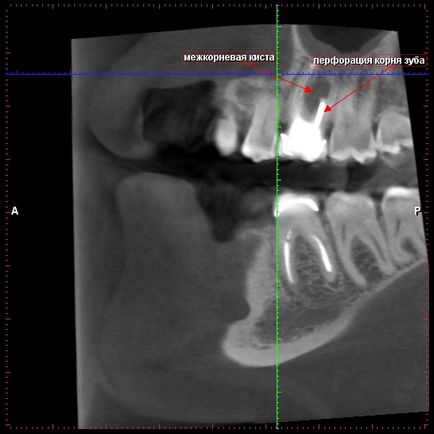

A perforáció a foggyökér és a ciszták keletkezését mezhkornevyh